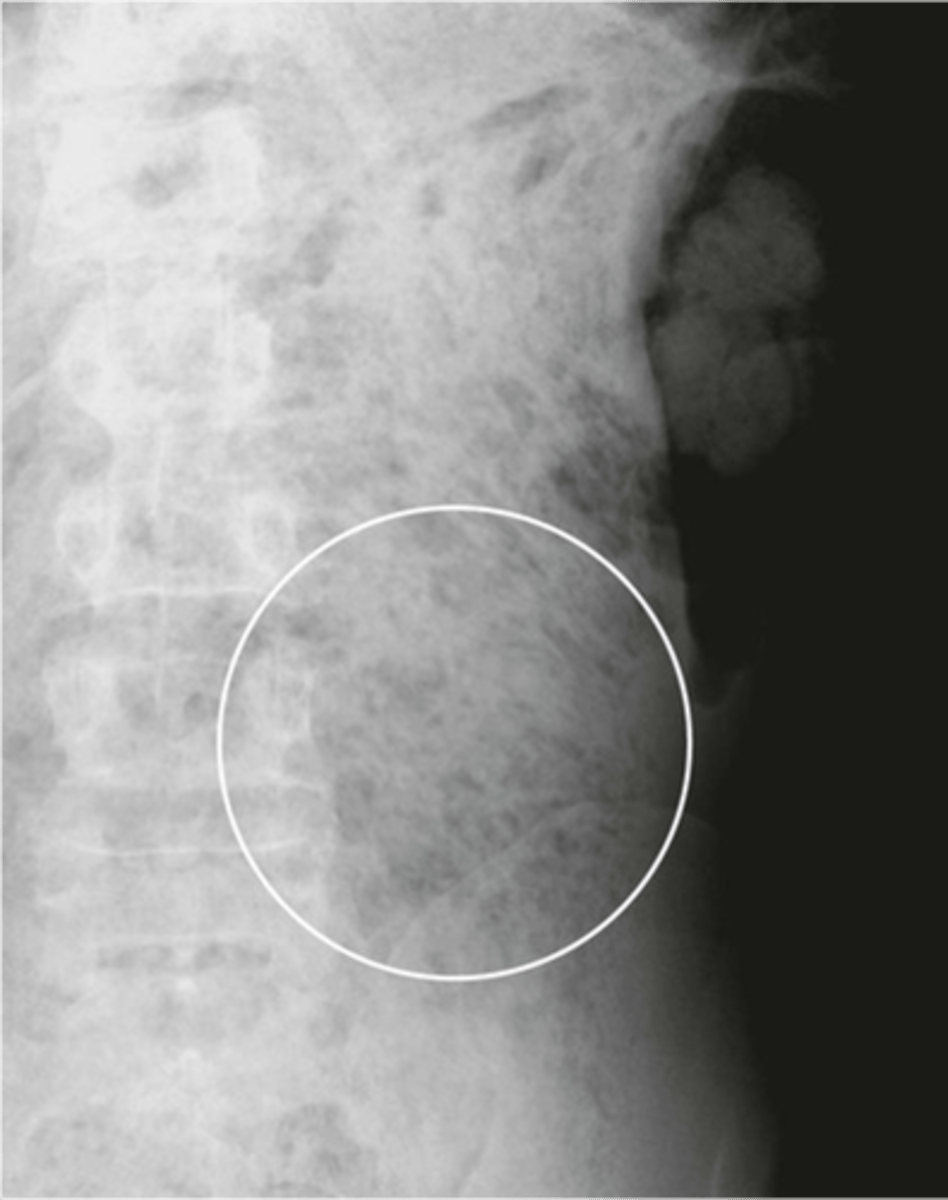

Abdominal aortic aneurysm calcification

Abdominal aortic aneurysm calcification (pic 2)

Abdominal aortic aneurysm calcification (pic 3)